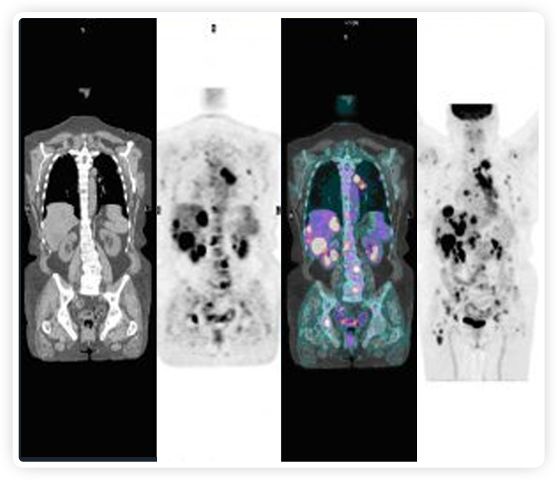

提起放療設備的引導系統,大家通常會想到結構性成像的CT或核磁。但你有沒有想過用功能性成像來引導放療呢?美國的一家醫療器械公司從2011年就致力于研究開發用PET提供生物學指導放射治療的設備BgRT。BgRT能實時利用癌癥的生物學特征作為信號指導治療全身腫瘤。

正電子發射斷層掃描(PET)是癌癥檢測中已建立的成像標準,與其他成像方式相比,PET能提供高靈敏度和特異性的圖像。

到目前為止,放射腫瘤學中(使用的圖像主要是結構性的,而PET圖像可以提供生物學信息。通過使用注射示蹤劑,例如18-FDG,PET可以描繪腫瘤的代謝活性,使其“點亮”。(FDG是用于可視化癌癥代謝的最廣泛使用的示蹤劑。與正常組織相比,腫瘤細胞保留更高水平的FDG。)不同的PET示蹤劑可以識別腫瘤的不同生物學特征,例如特定生物標志物抗原(例如,PSMA)或甚至探測免疫系統本身(例如,PDL1表達或活化的T細胞)。

RefleXion將PET成像與立體定向放射治療相結合。在注射示蹤劑后,RefleXion的技術基于示蹤劑信號實時地在一個或多個目標上引導治療性X射線。使用這種專有方法,RefleXion的平臺有可能比現有系統向癌癥病變提供更高劑量的輻射,并改善周圍健康組織的保護。

為了避免PET長圖像采集時間,RefleXion開發了一項專利技術使用重合的PET光子對來指導放射治療束,因為實時檢測發射的光子,為生物指導提供了一種時間有效的方法。